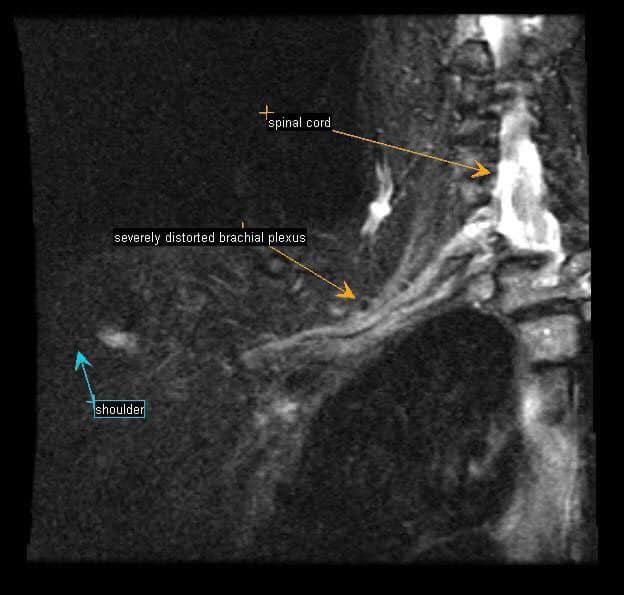

*Chụp cộng hưởng từ (MRI): Những hình ảnh này có thể giúp xác định vị trí và nguyên nhân gây ra ép các dây thần kinh của đám rối thần kinh cánh tay hoặc động mạch dưới đòn. Những hình ảnh quét cũng có thể tiết lộ bất kỳ dị tật bẩm sinh – chẳng hạn như một dải sợi kết nối xương sống của bạn với xương sườn hoặc xương sườn phụ có thể là nguyên nhân gây ra các triệu chứng.